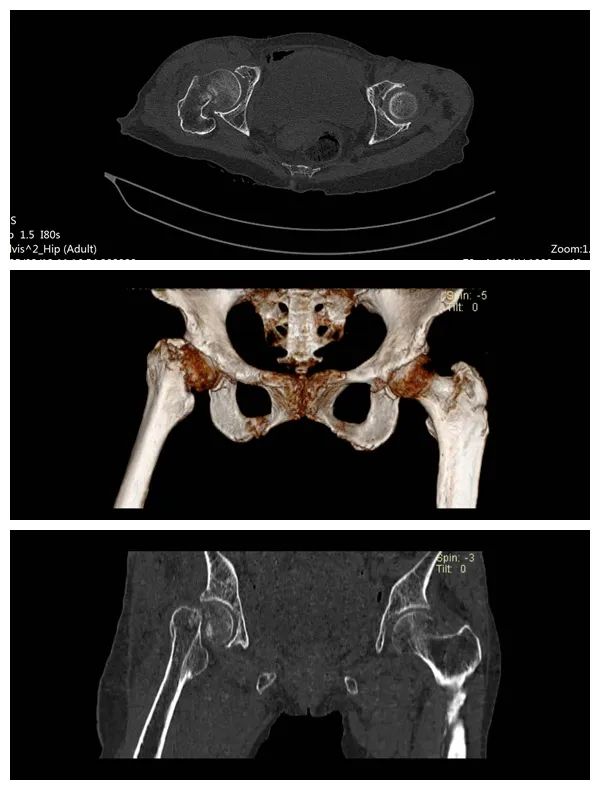

术前片

入院诊断:右侧股骨颈骨折、骨质疏松、双肺肺炎。